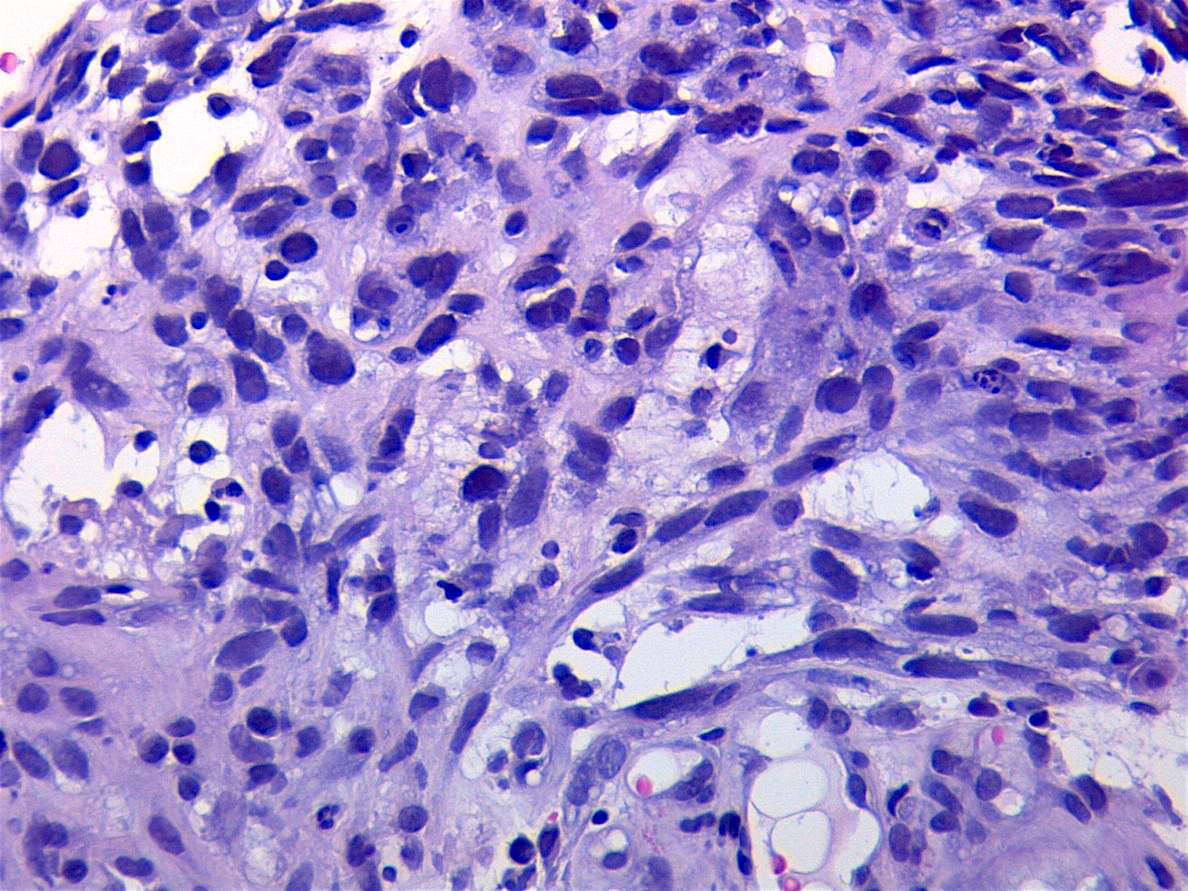

- Anaplasia is defined similar to anaplastic Wilms tumor as a significant nuclear variation (cells that are 3x larger than background tumor cells) and the presence of atypical multipolar mitotic figures

- It was historically a negative prognostic factor but this may no longer be true (Cancer 2008;113:3242, Eur J Cancer 2021;143:127)

- Anaplastic tumors often require more intensive treatment (Cancer 2008;113:3242)

- Anaplasia specifically requires multipolar mitotic figures

- Make sure you are not overinterpreting degenerating or apoptotic cells

- Look for organization of the division and exclude cells that appear to be exploding

- Also try to avoid interpreting overlapping cells as 1 larger cell

Microscopic (histologic) images

Contributed by Erdener Özer, M.D., Ph.D. and Mark R. Wick, M.D.

AFIP images - anaplastic rhabdomyosarcoma

A. 3x nuclear size variability and tripolar mitotic figures. Multipolar mitotic figures (including tripolar mitoses) and nuclear anaplasia (3x variation in nuclear size) are required to diagnose anaplastic embryonal rhabdomyosarcoma (ERMS). Solid growth pattern is irrelevant and necrosis can be seen in any subtype of rhabdomyosarcoma. ERMS typically displays the alternating pattern of hypocellularity and hypercellularity (also a buzzword for high grade malignant peripheral nerve sheath tumors). There is no requirement for a specific mitotic rate.